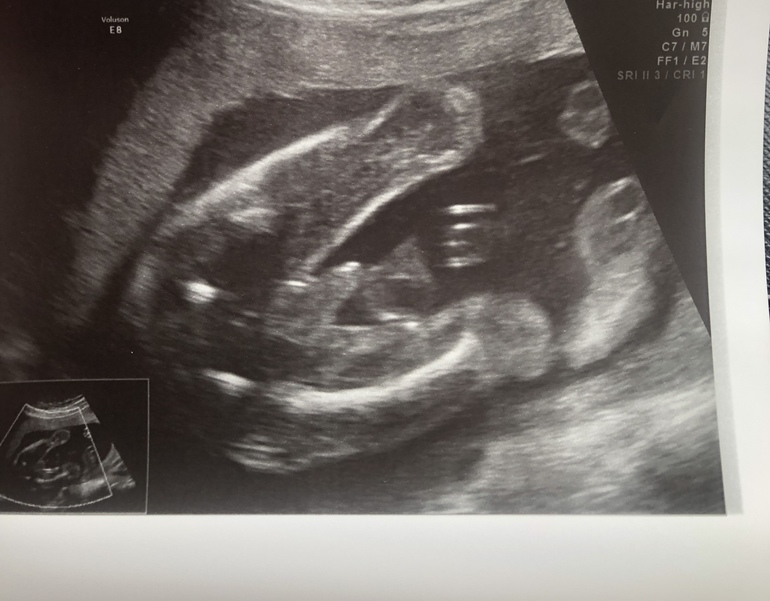

И это второй, вид снизу

На первом скрининге сказали мальчик 90-97%, не ошиблись